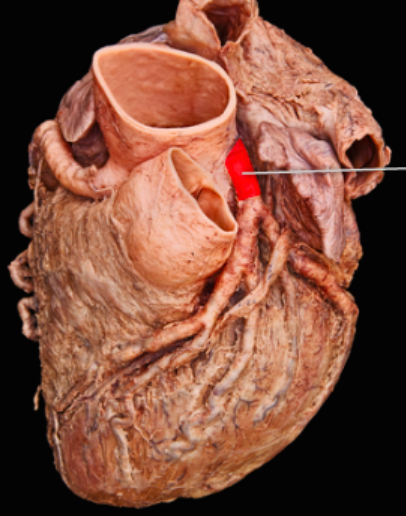

9

Q

A

Left Coronary Artery/ Left Main

10

Right Coronary Artery